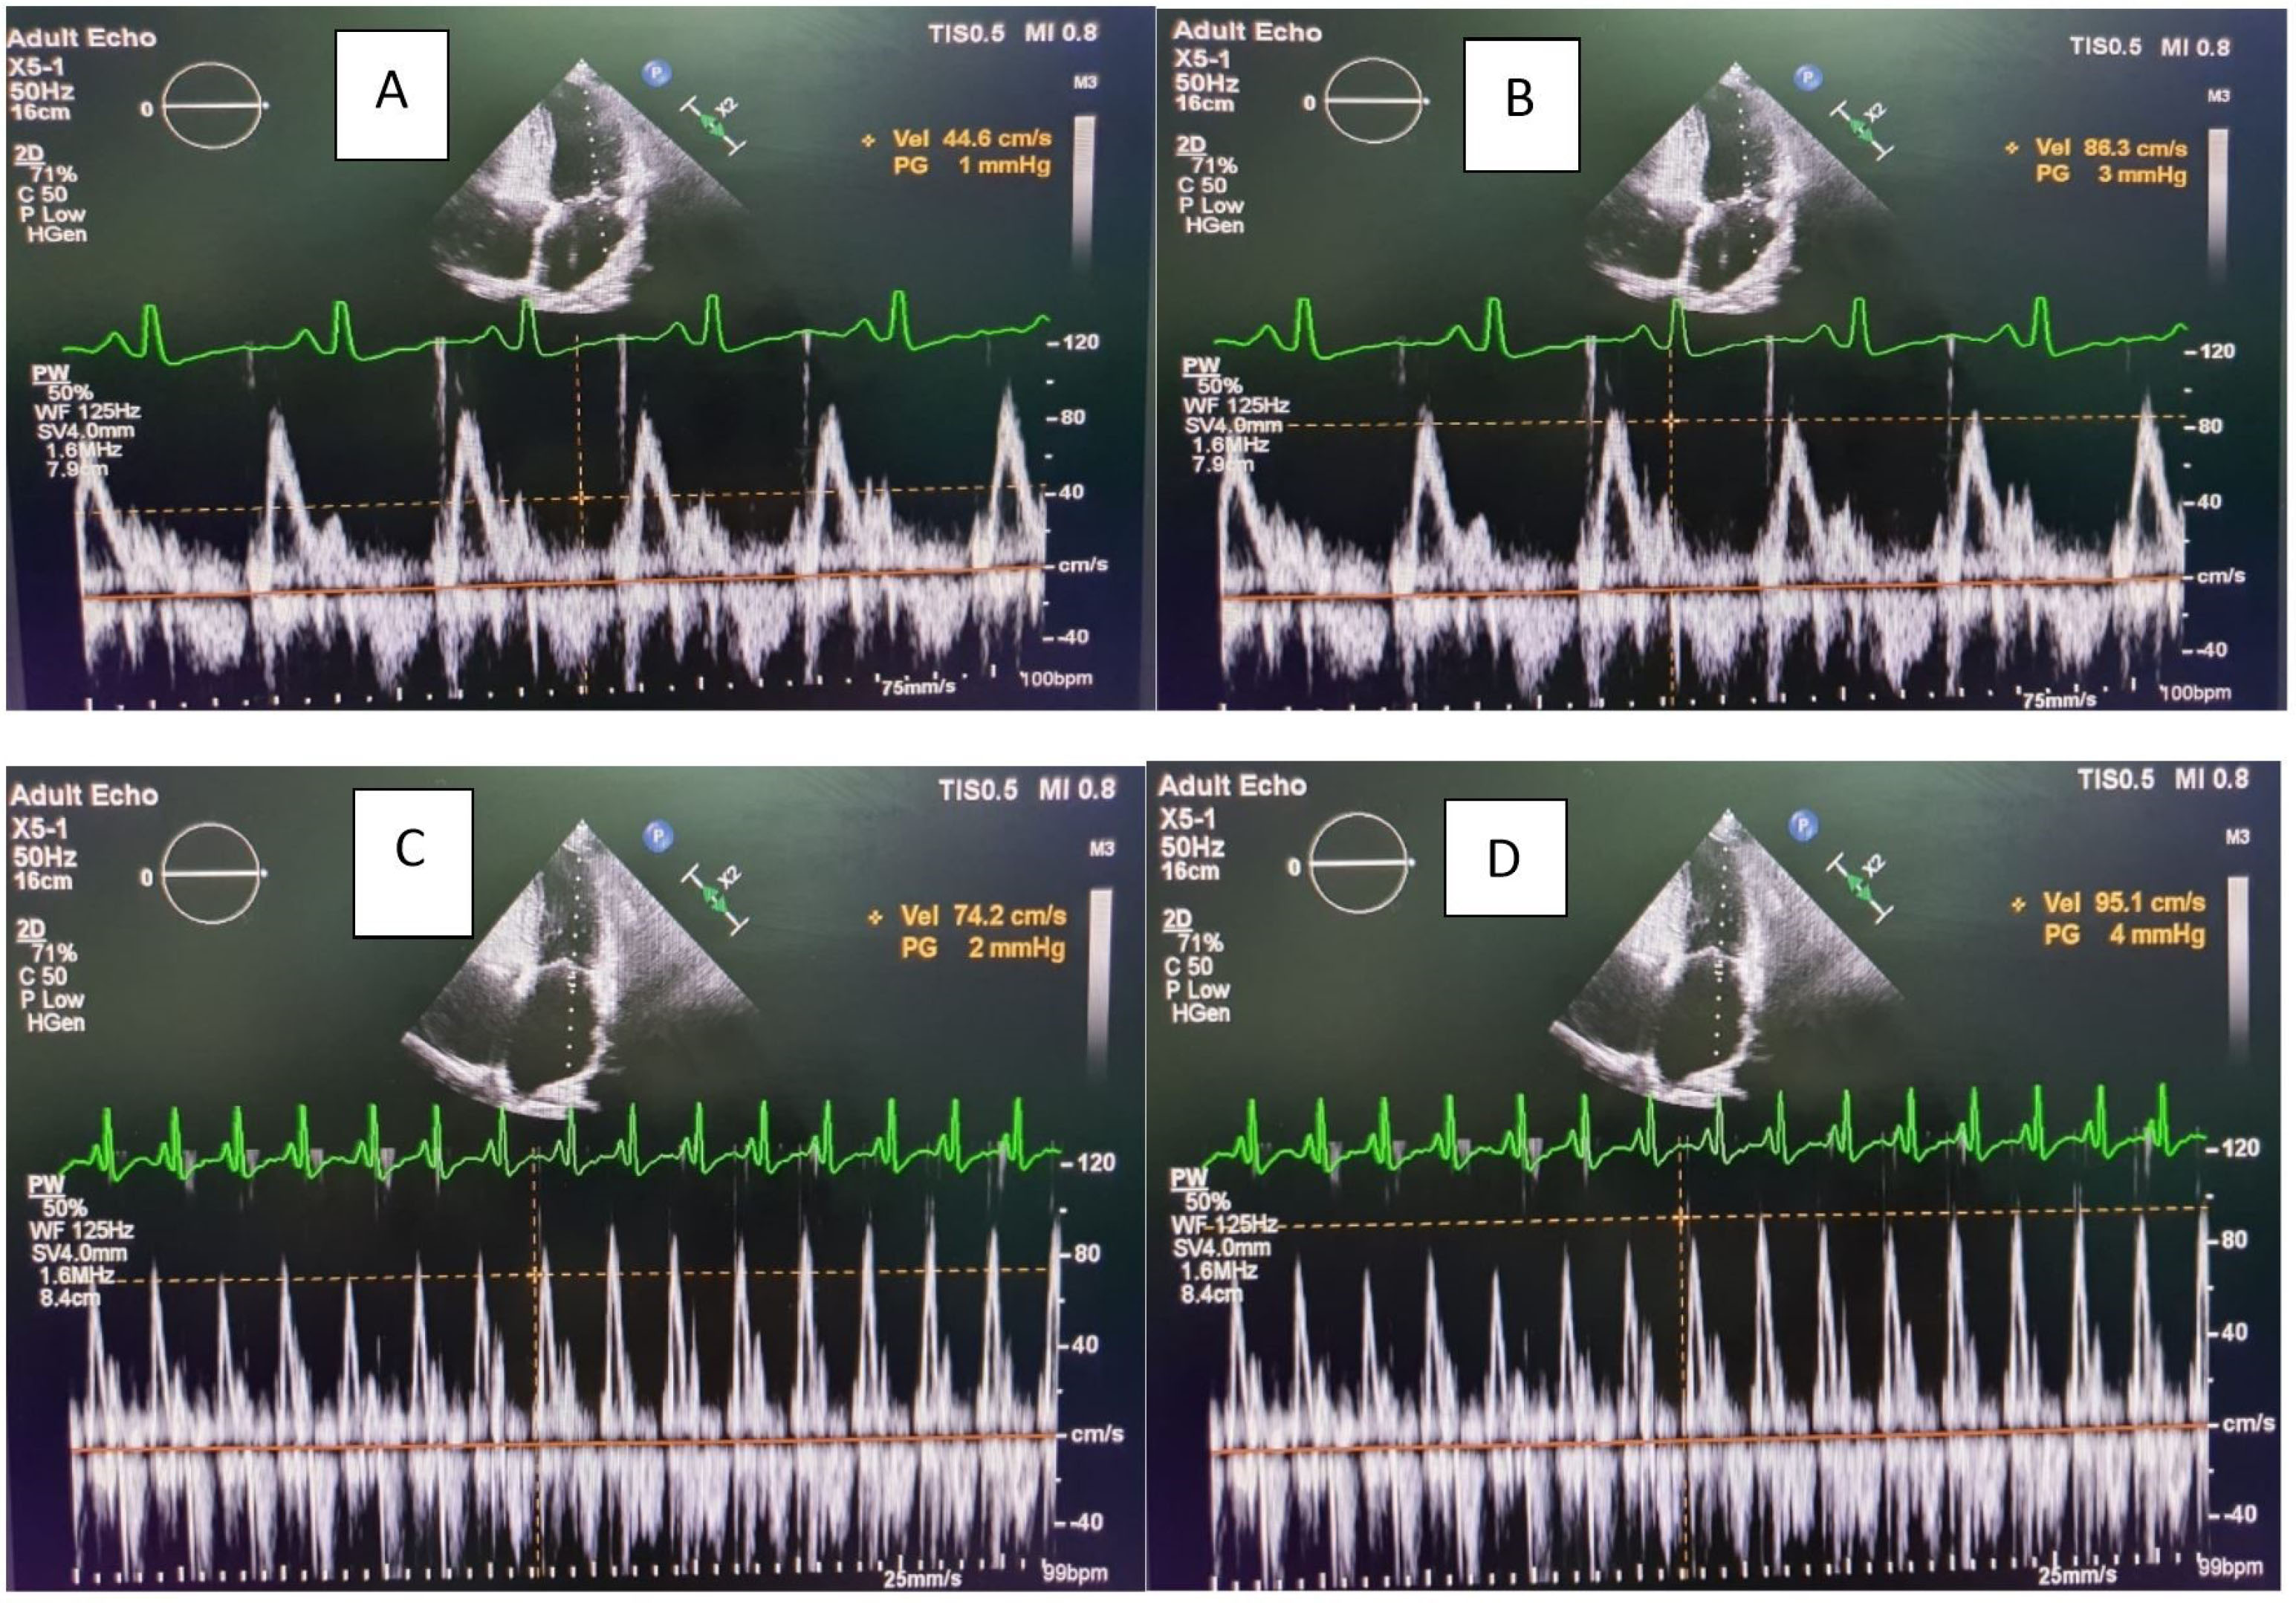

Figure 2. Image of tricuspid inflow region in a patient showing significant respiratory variation (A,B) pre- operatively as compared to the (C,D) post – operative

In CCP, ventricular filling is severely restricted and occurs only in early diastole with respiratory variation. This underlines the various hemodynamic changes unique to CCP. 15

The doppler echocardiography demonstrates respiratory variation in flow velocity across atrio-ventricular valve to point towards CCP. 16 This is due to the dissociation of intrathoracic and intracardiac pressures and ventricular interdependence.

The various echocardiographic parameters such as IVC congestion, mean LA size, mitral and tricuspid E velocity and TDI findings significantly improved in a study from central India comprising 23 patients of post-pericardiectomy. 17 In our study, there was significant respiro-phasic variation in the mitral and tricuspid E velocity in all patients (P < 0.001). Tissue Doppler imaging (TDI) is a useful for distinguishing CCP from restrictive cardiomyopathy. 18